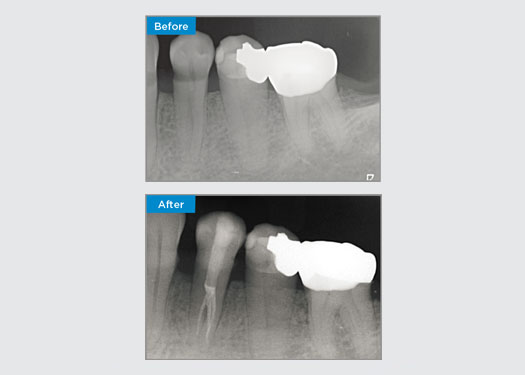

Este paciente se presentó con una restauración rota en el aspecto distal-oclusal de la pieza dental 46. La restauración existente del diente se extendió de manera muy profunda y cerca de la cámara pulpar. Dado el gran tamaño de la restauración, es muy probable que, si simplemente reemplazamos la restauración con otra restauración directa, el resultado sería el mismo, con la restauración rompiendo debajo de las cargas oclusales a las que se someten el diente y la restauración. Por lo tanto, se recomendó una opción indirecta para el diente. Dado que el tercio mesial del diente no se vio afectado en gran medida por el resto de una estructura dental sólida, podríamos preservarlo y ser mínimamente invasivos restaurando el diente con una restauración indirecta con el sistema CEREC

Dr. Sahil Soni, Queensland, Australia